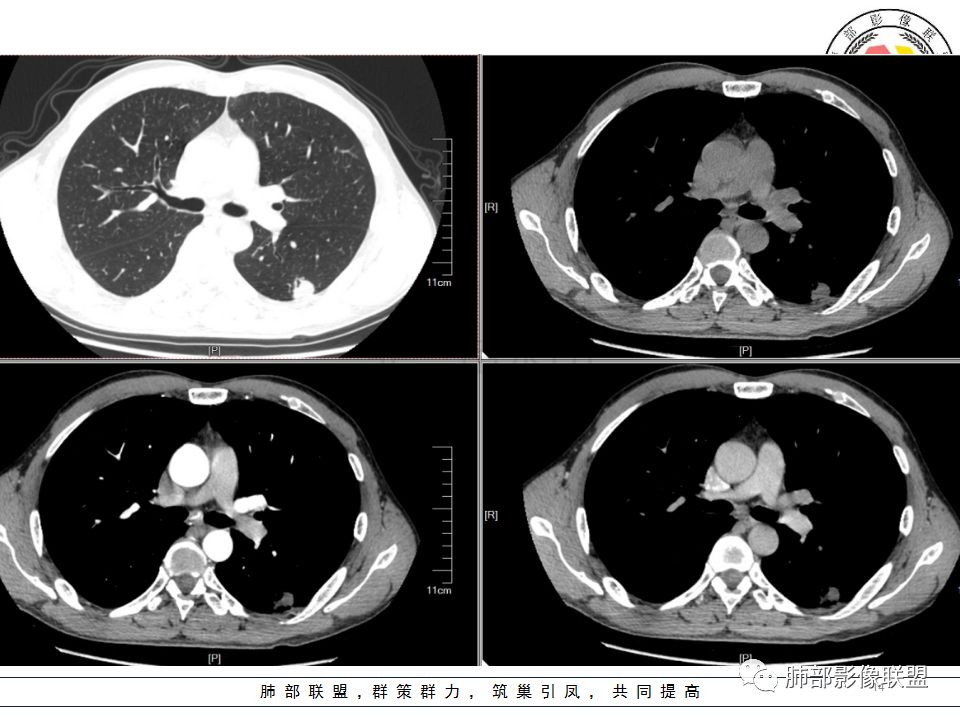

病历资料

左肺下叶背结节丶融合趋势,形态较单一,平直,无胸膜凹陷,目测轻强化,有支气管爬行丶子灶。诊断:TB>pC>腺癌。

左肺下叶结节,边缘平直为主,部分膨隆,卫星病灶,似乎无强化,糊墙,胸膜下脂肪间隙增宽,结核可能性大,腺癌待排。

左肺下叶背段孤立结节,长轴与胸膜平行,支气管近端截断,刀削平直,糊墙,卫星灶轻强化,考虑TB。

左肺下叶背段小结节 ,糊墙 ,胸膜外脂肪间隙增宽 ,引流支气管壁厚 ,有爬行征 ,病灶无明显强化,考虑结核可能。

考虑结核,左肺下叶病灶,强化不明显,胸膜反应性增厚,有卫星灶,强化不明显。

病史:男,50岁,胸痛15天,无抽烟;胸膜下病灶,有可能相关;

影像:病灶不规则,形态奇特,矢状位可能看到病灶的真实形态;上面近端病灶似乎与主病灶不相连续,多病灶?内侧似乎小花小草,疑为卫星灶;胸膜下病变,与胸膜关系不密切,胸膜线状强化;强化方式渐进性,感觉不均匀,也许是伪影;病灶凹陷平直不膨隆,考虑良性。诊断:结核;鉴别:腺癌(近胸膜端三个胸膜反应凹,偏上部层面毛刺不能除外,但其他地方没有,整体收缩力还比较弱,无钙化,考虑没有形成钙化和纤维化。

男性,胸疼,左肺下叶背段结节,边缘光滑,有平直收缩,轻度延迟强化?胸膜肥厚,有轻度胸膜牵拉,周围有卫星灶,考虑炎性病变,结核,隐球可能性大。鉴别腺癌。

左肺下叶背段结节,边缘较光整,平直,近端支气管未见明确截断征象,沿支气管走行,临近胸膜局限性增厚,增强目测未见明确强化,周围见稀疏小树芽分布,整体考虑良性病变,结核放前考虑。

男,50岁,左肺下叶结节影,似乎两个结节,相邻,上面一个偏内,有分叶,下面一个偏外,胸膜下,内侧有稍增厚的支气管影,并且支气管进入病灶内,周围有更小卫星灶,外侧有胸膜增厚,糊墙。总的来说,考虑炎性病灶,结核可能性最大。但靠内侧的结节有恶性特征,腺癌待排。

50岁男性,吸烟,胸痛15天。左肺下叶胸膜下结节,边缘平直为主,部分膨隆,但似乎呈山丘,沿支气管爬行,周围是卫星灶还是小花小草,考虑恶性,小细胞癌可能性大,结核待排。

左肺下叶背段结节,边缘光滑,有平直收缩,强化不明显,胸膜肥厚,有轻度胸膜牵拉,周围有卫星灶,考虑感染性病变,结核首选。

左肺下叶背段结节,形态近似两个结节融合或靠近,沿支气管走行分布,近侧支气管内见条状软组织,增强未见明确强化,周围见小树芽,首先考虑结核,鉴别小。

患者中年男性,因胸痛半月入院。查血常规、凝血功能、肾功能正常。有抽烟史。胸部CT:左肺下叶背段胸膜下与胸膜垂直长条形不规则病灶,支气管爬行改变,边缘欠清楚,部分层面呈葫芦样见血管集束征、周围点状卫星灶,增强无明显强化,左肺门淋巴结肿大。综合常规结核可能性大,其次小细胞肺癌。鉴别其他。

左肺下叶病变,边缘平直,似有U形凹陷,树芽及卫星病灶,支气管爬行征?无明显强化,考虑结核。

左肺下叶背段近胸膜下结节,部分边缘平直并可见卫星灶,增强后强化不明显,首先考虑结核。

中年男性,左肺下叶背段结节,内可见支气管充气征,周围有晕,周围有结节,局部胸膜增厚,可见脂肪间隙。考虑良性病变可能,隐球?,鉴别结核;病灶有沿支气管生长趋势,气道阻塞,经皮肺穿除外肺癌。

中年男性,胸痛,吸烟史。左肺下叶背段结节,边界清楚,局部见小毛刺及胸膜牵拉,部分层面成葫芦形,局部与胸膜宽基底相贴,邻近胸膜增厚。近端支气管达病灶边缘处,似略增厚。周围见少量卫星微结节及树丫。增强扫描无强化。考虑:1,结核:支持点有发病部位,邻近卫星灶及树丫,近病灶边缘支气管壁似略增厚,邻近胸膜增厚。不支持点,引流支气管壁增厚范围不够长。2,小细胞癌:支持点有局部葫芦形,似沿支气管向肺门区扩展。3,腺癌:支持点有毛刺和胸膜牵拉,当然结核也可以有这两个征象。不支持点有无强化。